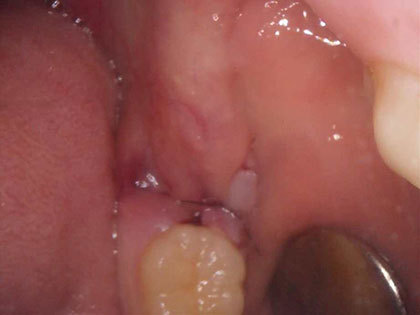

抜歯後の写真がこちら

左右それぞれ歯が萌出中(歯肉を突き破って歯がでてきている)

左下は器具をひっかけると、すぐ歯が脱臼して抜歯出来ます。

右下は少し歯肉を切開し、歯冠(頭の部分)を削り、歯根(根っこの部分)を引っ張りだして抜歯しました。

最後に洗浄し、糸で縫い止血しました。